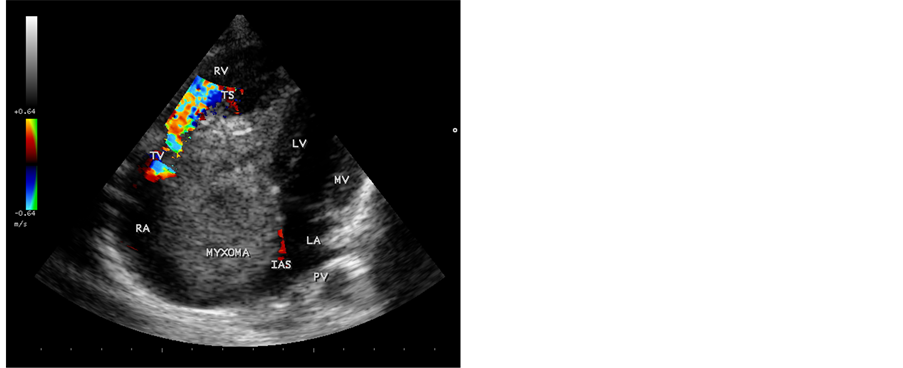

A 12-year-old male child was suffering from low grade fever, joint pains and weight loss for the past two years. He was on penicillin prophylaxis with a suspicion of Rheumatic fever by a local practitioner during this period. Since he developed dyspnea, vomiting episodes and dizziness in the school while sitting in the class room suddenly, he was referred to this hospital. General examination revealed no abnormal findings. His heart rate was 96 bpm and blood pressure was 110/80 mmHg. Physical examination revealed loud first heart sound, a mid diastolic murmur in the lower left sternal edge and a soft midsystolic murmur in the second left intercostal space. The second heart sound was inaudible. These features are consistent with tricuspid and pulmonary valve stenoses and clinically masquerading as right sided obstructive lesions such as Ebstein anomaly, Rheumatic tricuspid valve disease and congenital pulmonary valve stenosis. Lung fields were clear. Blood chemistry revealed normal. ECG revealed large P wave and X-ray chest showed right atrial enlargement and a prominent main pulmonary artery with diminished vascular markings. CT abdomen was normal. Transthoracic 2D echocardiography revealed a large myxoma occupying in the right atrium measuring 69.5 mm × 38.1 mm size with an attachment to the interatrial septum. It is prolapsing through the tricuspid valve into the right ventricle as shown in Figure 1 and extending into the right ventricular outflow tract in Figure 2. It is protruding into the pulmonary artery through the pulmonary valve in Figure 3. Color-flow Doppler Figure 4 and Figure 5 revealed tricuspid and pulmonary valve obstructions as mild to moderate stenoses. The child responded to steroids. He developed the similar symptoms after one week, which are intermittent in nature and died suddenly when leaning forward while washing his face in the early morning hours due to a syncopal episode before planning to surgical removal of the tumor. Echocardiographic screening of family members were normal.

Figure 4. Color-flow Doppler imaging―Apical 4 chamber view, showing the tricuspid valve obstruction as moderate tricuspid stenosis.

Figure 5. Color-flow Doppler imaging―Short axis view, showing the pul- monary obstruction as moderate pulmonary valve stenosis.

In this case report, a large right atrial myxoma, 69.5 mm × 38.1 mm in size, with a basal attachment to the entire portion of interatrial septum, prolapsing into right ventricle through the tricuspid valve and it’s floating part protruding into the main pulmonary artery in a 12-year old male child was visualized by transthoracic 2D echocardiography. Figures 1-3 revealed the myxoma occupying in the right atrium and prolapsing into the right ventricle through the tricuspid valve, extending into the right ventricular outflow tract and protruding into the pulmonary artery through the pulmonary valve. Color-flow Doppler Figure 4 and Figure 5 revealed the tricuspid and pulmonary obstructions as moderate stenosis of the valves.